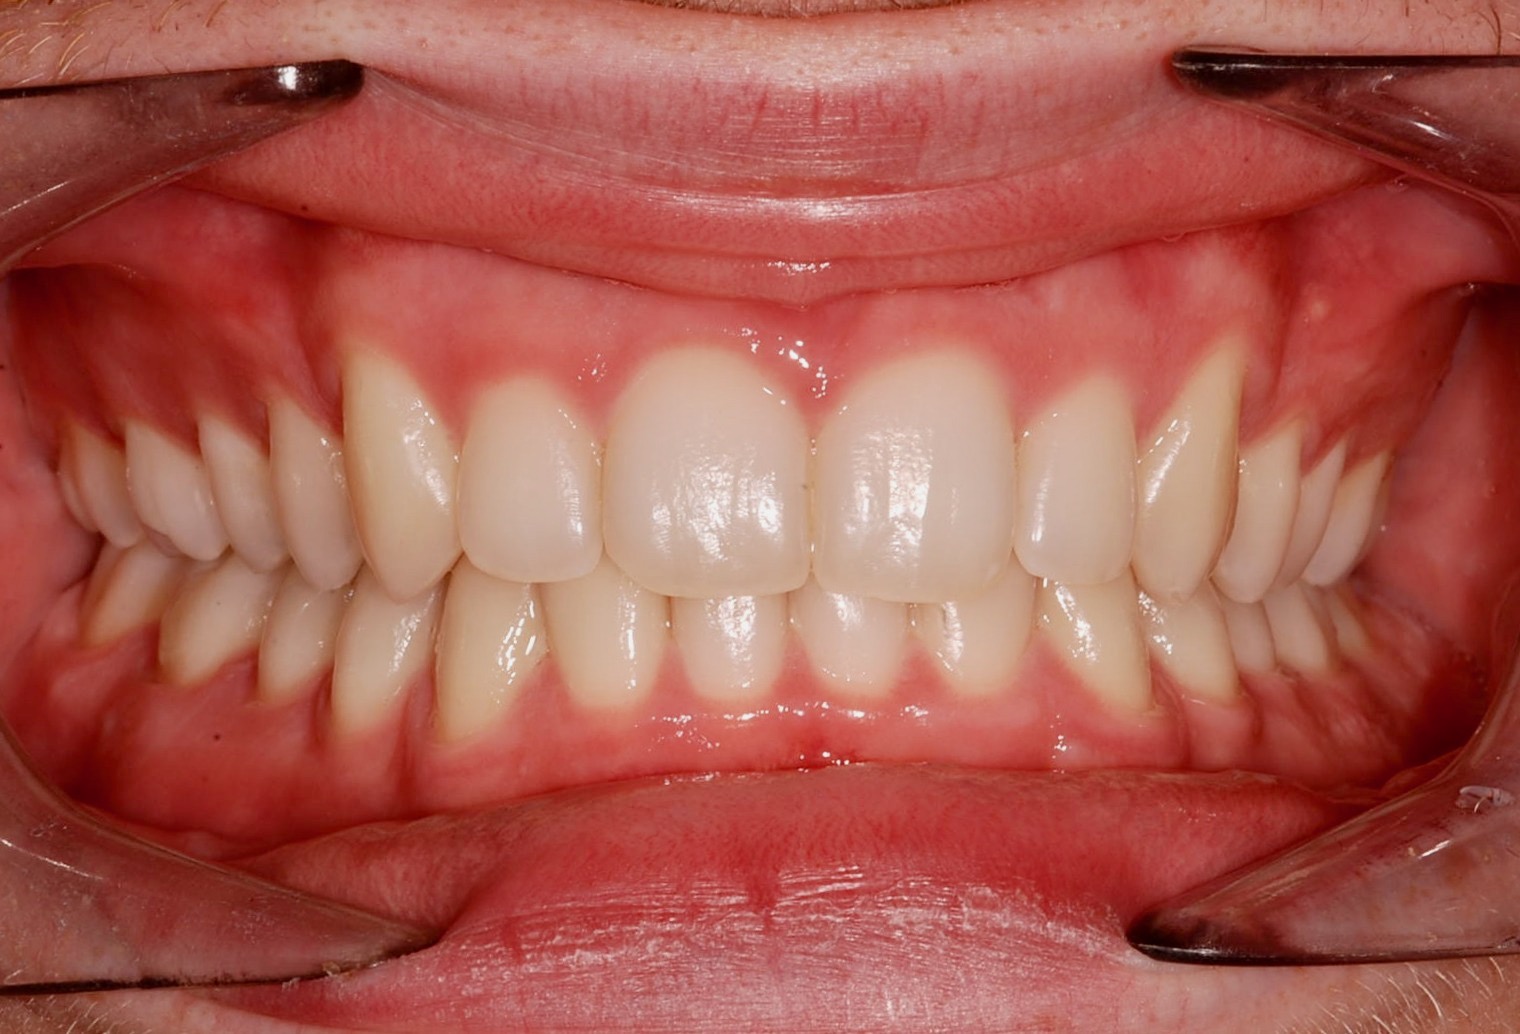

Class II subdivision malocclusions can be difficult to treat because of their asymmetric occlusal relationships. An accurate diagnosis, etiologically based when possible, is essential to perform a correct and efficient orthodontic treatment.

The aim of this article is to illustrate a case report treated with customized lingual brackets in association with a simple vestibular device.